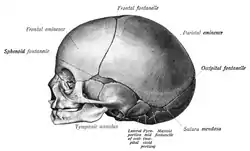

Cranial sutures

The mesenchyme above the meninges undergoes intramembranous ossification forming the neurocranium.[3] The neurocranium consists of several bones, which are united and at the same time separated by fibrous sutures.[3] This allows movement of the separate bones in relation to one another; the infant skull is still malleable.[3] The fibrous sutures specifically allow the deformation of the skull during birth[3] and absorb mechanical forces during childhood[6] They also allow the necessary expansion during brain growth.[3]

In the very first years of life the sutures serve as the most important centers of growth in the skull.[3] The growth of the brain and the patency of the sutures depend on each other.[54] Brain growth pushes the two sides of the patent sutures away from each other, thereby enabling growth of the neurocranium.[54] This means that the neurocranium can only grow if the sutures remain open.[54] The neurocranium will not grow when the forces induced by brain growth are not there.[12] This will occur for example when the intracranial pressure drops; the sutures do not experience stretching anymore causing them to fuse.[17]